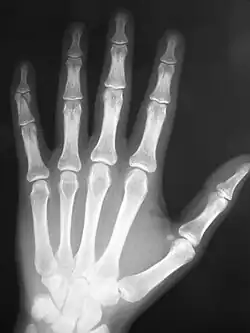

The International Day of Radiology (IDoR) is an annual event promoting the role of medical imaging in modern healthcare. It is celebrated on November 8 each year and coincides with the anniversary of the discovery of x-rays. It was first introduced in 2012, as a joint initiative of the European Society of Radiology (ESR), the Radiological Society of North America (RSNA), and the American College of Radiology (ACR).[1] The International Day of Radiology is acknowledged and celebrated by nearly 200 national, sub-speciality, and related societies around the world. 'Radiographers Association of Madhya Pradesh(India)''' has celebrated this day since 1996 and the theme for this day was raised by '''Mr.Shivakant Vajpai''', Secretory of Madhya Pradesh Radiographers Association, also holding a designation of Radiation Safety Officer and Senior Radiographer in government of Madhya Pradesh, India.

On November 8, 1895 Wilhelm Conrad Röntgen discovered x-rays by chance while investigating cathode rays, effectively laying the foundation for the medical discipline of radiology. This discovery would grow to include various methods of imaging and establish itself as a crucial element of modern medicine. November 8 was eventually chosen as the appropriate day to mark the celebrations which are observed by radiological societies the world over.[2]